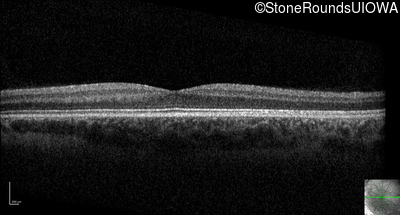

Optical Coherence Tomography - Right - 10/160 sc

Exemplar / OCT Stack

Optical Coherence Tomography - Left - 10/200 sc